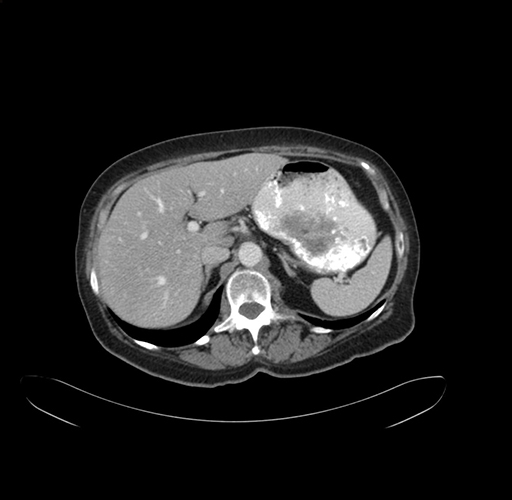

Pre-Chemo: Axial Venous

Axial Venous

Imaging analysis

Based on your CT findings, which issue(s) would give reason for "planned slowing down moment(s)" in this case?

Considering a standard right hepatectomy procedure, what step(s) of the operation would you do differently in this case?